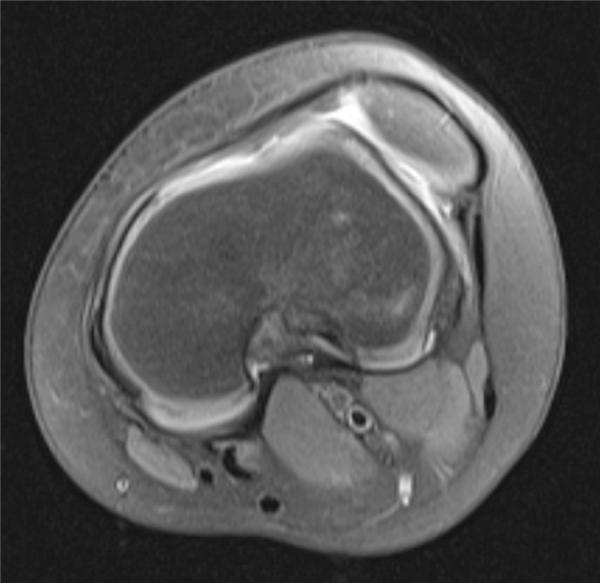

Congenital patellar dislocation is a rare condition in which the patella is permanently dislocated and cannot be reduced manually. The patella develops normally as a sesamoid bone of the femur. This congenital dislocation results from failure of the internal rotation of the myotome that forms the femur, quadriceps muscle and extensor apparatus. It usually manifests immediately after birth, although in some rare cases, the diagnosis may be delayed until adolescence or adulthood. Early diagnosis is important, thereby allowing surgical correction and avoiding late sequelae, including early degenerative changes in the knee. A case of permanent dislocation of the patella is presented here, in a female child aged seven years.

先天性髌骨脱位是一种罕见的病症,即髌骨永久性脱位且无法手法复位。髌骨作为股骨的籽骨正常发育。这种先天性脱位是由于形成股骨、股四头肌和伸肌装置的肌节内旋失败所致。它通常在出生后立即出现,不过在一些罕见病例中,诊断可能会延迟至青春期或成年期。早期诊断很重要,这样才能进行手术矫正并避免晚期后遗症,包括膝关节的早期退行性改变。本文介绍了一例七岁女童永久性髌骨脱位的病例。